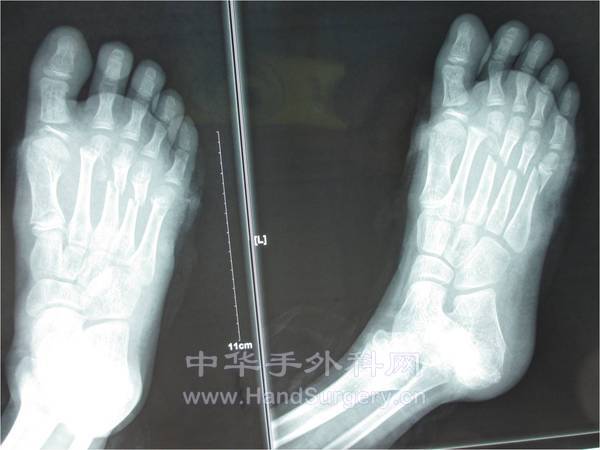

患者男性,8岁,于2013年2月23日因外伤在外院就诊,行:“清创,骨折内固定术及VSD负压吸引术”,术后VSD更换3次,并告知右小趾已坏死需截趾,患者拒绝遂转入我院,予以拆除VSD见小趾已坏死,告知患者次日手术,因右小趾已坏死需截除,创面需行皮瓣或人工皮覆盖。患者家属拒绝截趾,转回原医院。被告知需截除右足至第五跖骨,外露创面用小趾废弃皮覆盖后剩余创面植皮,患者家属遂崩溃,后再次来我院咨询就诊,考虑患者为小儿,第五跖骨头截除影响负重行走,遂收入院,于2013/3/25行皮瓣修复。术中见右第五跖骨表面已较多氧化、发黑,关节囊等已坏死,右小趾坏死。术中刮除右第五跖骨表面坏死骨,短缩右小趾至近节远端。目前术后第七天皮瓣顺利渡过危险期。